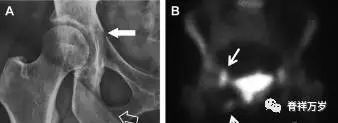

具有持续损伤因素的耻骨支骨折,可能看似轻微,尤其是合并骨质疏松的患者。因此,特别需要注意皮质缺损和骨密度改变。长跑运动员易发生耻骨应力性骨折,常常发生在靠近耻骨联合的下支。由于这些骨折为非移位骨折,所以常常被忽视。

图 2 自行车事故患者,侧方受力的髋臼前柱/耻骨骨折。A 正位平片示右侧髂耻线轻微中断(实箭头),此处异常最初并未发现。此外,右下方其实还有一处轻微耻骨支骨折(空箭头)。B 10天后行骨闪烁显像证实了髋臼前柱骨折和侧耻骨下支骨折(箭头)。值得注意的是,左侧前柱亦存在异常